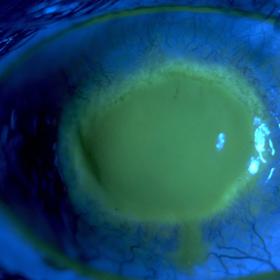

Akantamébová keratitida a střečci

Akantamébová keratitida nastává, když améba infikuje rohovku - průhlednou vnější vrstvu oka. Tento drobný vetřelec pak může způsobit slepotu trvalým zjizvením či dokonce roztavením. Příznaky jsou jako u obyčejné oční infekce. Rozmazané vidění, zarudnutí a citlivost na světlo. Postižený může mít také pocit, že se mu v oku „něco zachytilo“. Do nejrizikovější skupiny patří lidé s kontaktními čočkami (améba dokáže přežít v prostoru mezi okem a čočkou). Sprchování či horká vana v kombinaci s nasazenými čočkami zvyšuje riziko infekce.